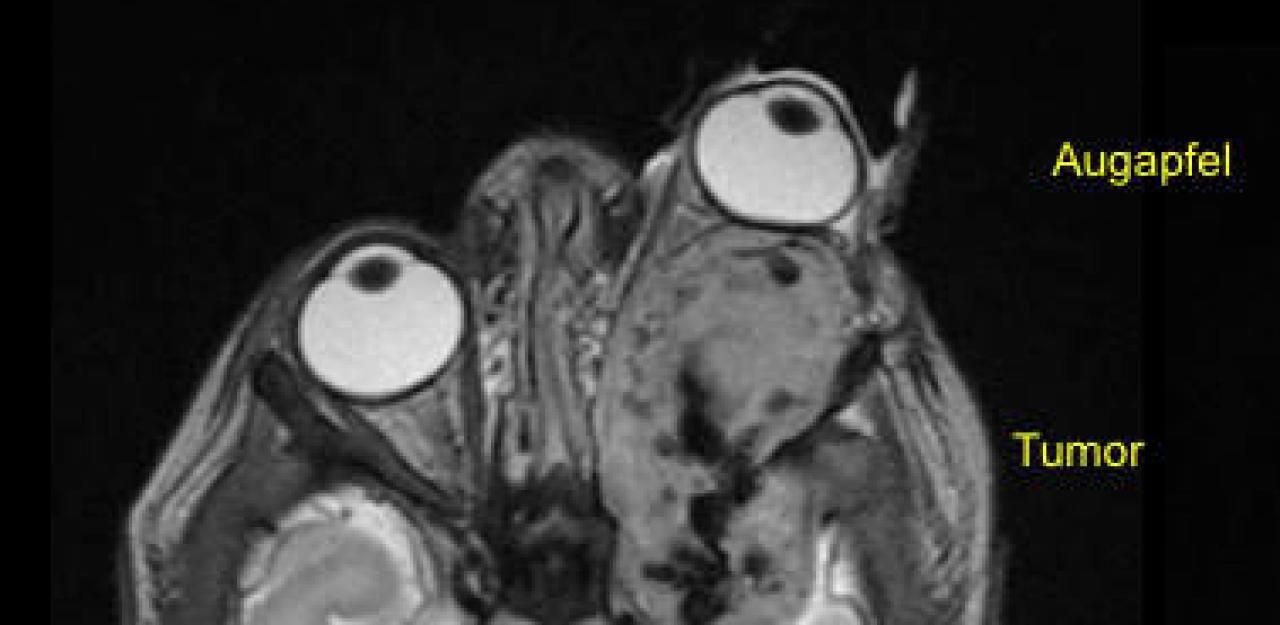

Den Grund für die Fehlbildung finden die Ärzte schnell heraus: Ein bösartiger Weichteiltumor, in der Fachsprache infantiles Fibrosarkom genannt, breitete sich in der gesamten Augenhöhle aus und drückte zudem auf das Gehirn. "Mit seiner großen Ausdehnung und der Nähe zu wichtigen Strukturen wie dem Sehnerv und dem Gehirn war der Tumor nicht operierbar", so Gerber. Doch die Ärzte mussten handeln. Der Tumor brachte den Säugling in Gefahr.

Ein Chemotherapie wird angeordnet, worauf der Tumor zwar etwas kleiner wird. Die Therapie ist für den kleinen Körper aber sehr strapaziös, es kommt zu Darmblutungen. Die Augenpflege gestaltet sich zudem schwierig und extrem aufwändig. Noahs Fall wird an einem Ärztetreffen besprochen. Das Kinderspital Zürich hatte soeben als einziges Kinderkrebszentrum der Schweiz im Rahmen einer internationalen Studie Zugang zu einem neuen zielgerichteten Medikament erhalten, von dem man wusste, dass es bei solchen Tumoren helfen könnte.

"Wir stellten fest, dass der Tumor in Noahs Augenhöhle jene genetische Veränderung aufwies, die es für die Wirkung des Medikaments brauchte", sagt Gerber. Obwohl die Ärzte mit diesem Ansatz neue Hoffnung schöpften, Noah zu heilen, herrschte Ungewissheit über die Erfolgschancen.

Doch diese trat nicht ein. Bereits zehn Tage nach Beginn der Therapie hatte sich das Auge deutlich in die Augenhöhle zurückgezogen. Der Tumor schrumpfte, Monat um Monat. Noah ist mittlerweile über ein Jahr alt. Das Medikament wirkt noch immer, Nebenwirkungen hat der Bub keine.